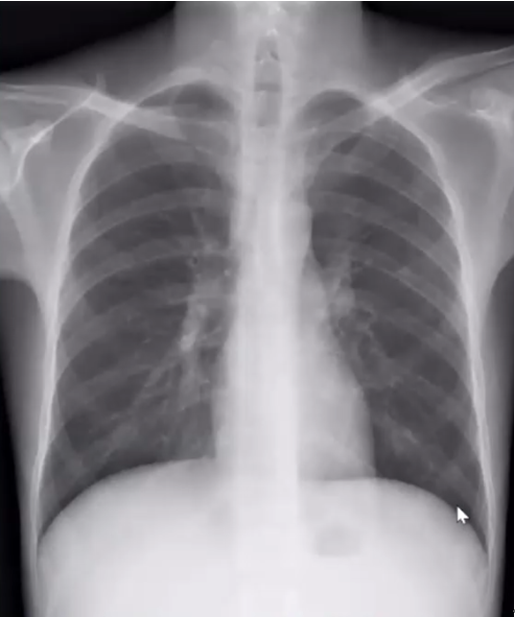

下图为一肿块,周围有晕征,中间有小气泡,增强扫描可见大片坏死,没有强化(图19),这种特征非常像曲霉感染,但最终穿刺病理证实为毛霉感染。其破坏范围更广。临床上,在诊断不清的情况下,一定要做增强扫描,能够帮助确定组织强化的程度。患者出现了胸腔积液,其中的小气泡更大,这是毛霉的特征。

图片

图19  毛霉感染

毛霉感染患者胸部CT可见反晕征,有胸腔积液,说明病变侵犯力非常强。其次,病变中的分隔粗大,其中的小气胞分布范围广。另外,病变中没有看到气液平面。但是由于病灶的破坏力更强更快,毛霉的生长跟不上,坏死物固定相对较弱,所以其病变破坏更多向外扩张,对血管的破坏性更大,因此我们看到很多低密度影。这是毛霉的特征。毛霉破坏组织后产生一些组织残留,因此CT上可见很多分隔(图20,图21)

图20  毛霉感染—反晕征,胸腔积液,分隔粗大

图21  毛霉感染—病变范围广、反晕征、胸腔积液